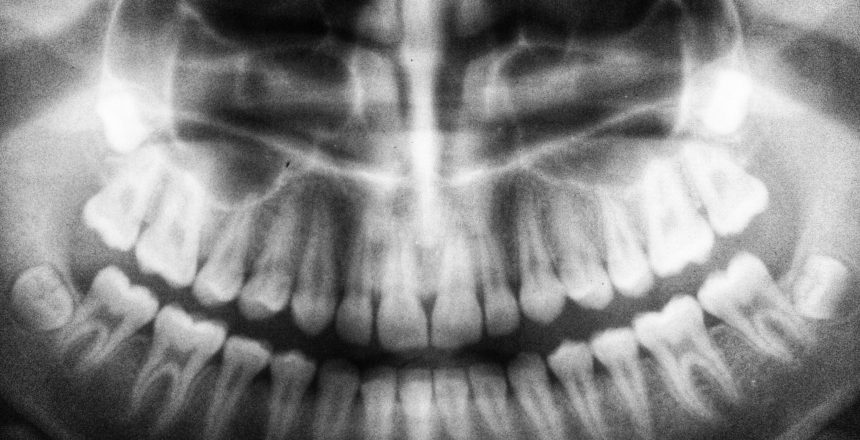

A cirurgia ortognática é uma técnica utilizada para corrigir alterações de crescimento dos maxilares.

Essas anomalias dentofaciais podem originar distúrbios da mordida, articulações e respiração, e também repercutir na estética facial.

A cirurgia ortognática é um procedimento realizado para corrigir e reposicionar os ossos da mandíbula.

A maxila é o osso responsável por suportar os dentes superiores e a mandíbula, os inferiores.

No entanto, por diversas causas, principalmente genéticas, algumas pessoas desenvolvem as estruturas com maior discrepância entre elas.

Nesse sentido, a cirurgia ortognática corrige o posicionamento dentário de pacientes que apresentam diferentes graus de assimetria na região.

Todo esse planejamento é feito antes da cirurgia, de forma digital, com auxílio de exames de imagens.